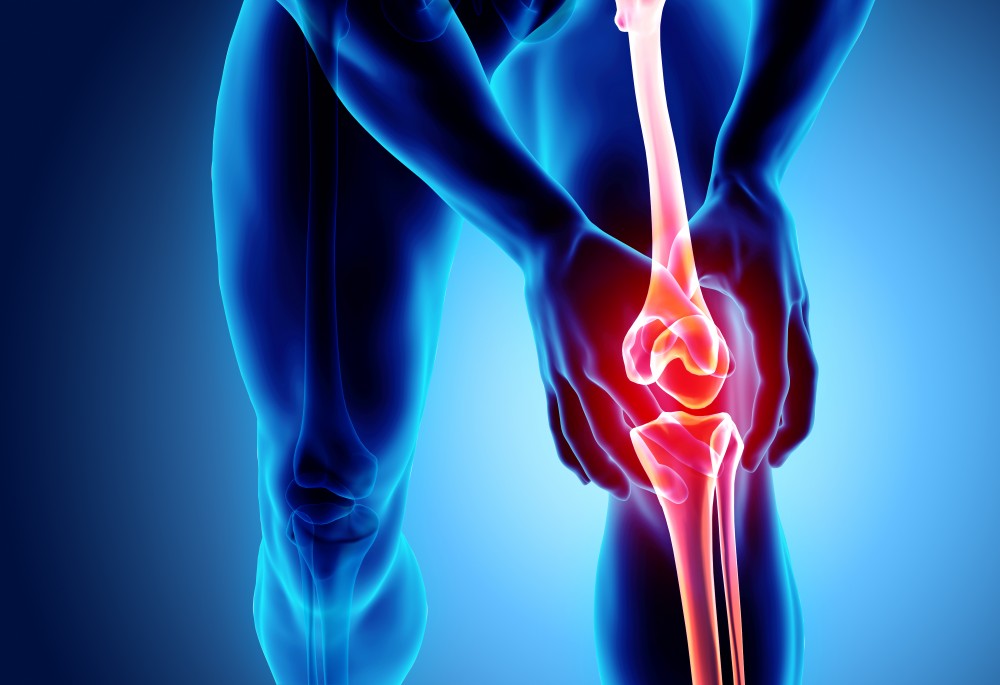

A kezelés végezhető a térden, bokán, csípőn, vállon is. Az eddigi eredmények kimagasló javulást mutatnak a tünetek enyhülésében, a fájdalom csökkenésében, és ennek következtében bizonyos esetekben a protézis beültetés elkerülhető. Ez a könnyen kezelhető rendszer arra lett kifejlesztve, hogy a zsírszöveteket kinyerjék, akár 20 perc alatt feldolgozzák és ugyanazon sebészi eljáráson belül vissza is ültessék a kezelésre szoruló területbe.

Térdízületi protézis beültetés